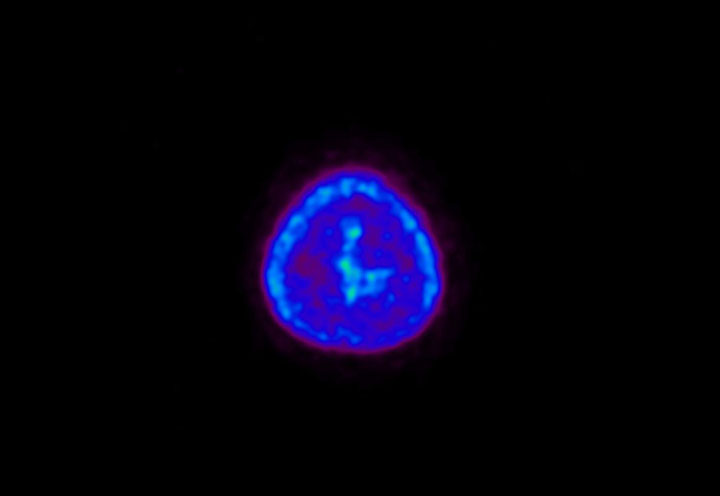

Head / Case5 : Amyloid

Axial

Courtesy : Kindai University Hospital

- Imaging protocol

- Injected dose: 4.27 MBq/kg, 18F-Flutemetamol

- Uptake time: 99 minutes

- Scan time: 20 minutes